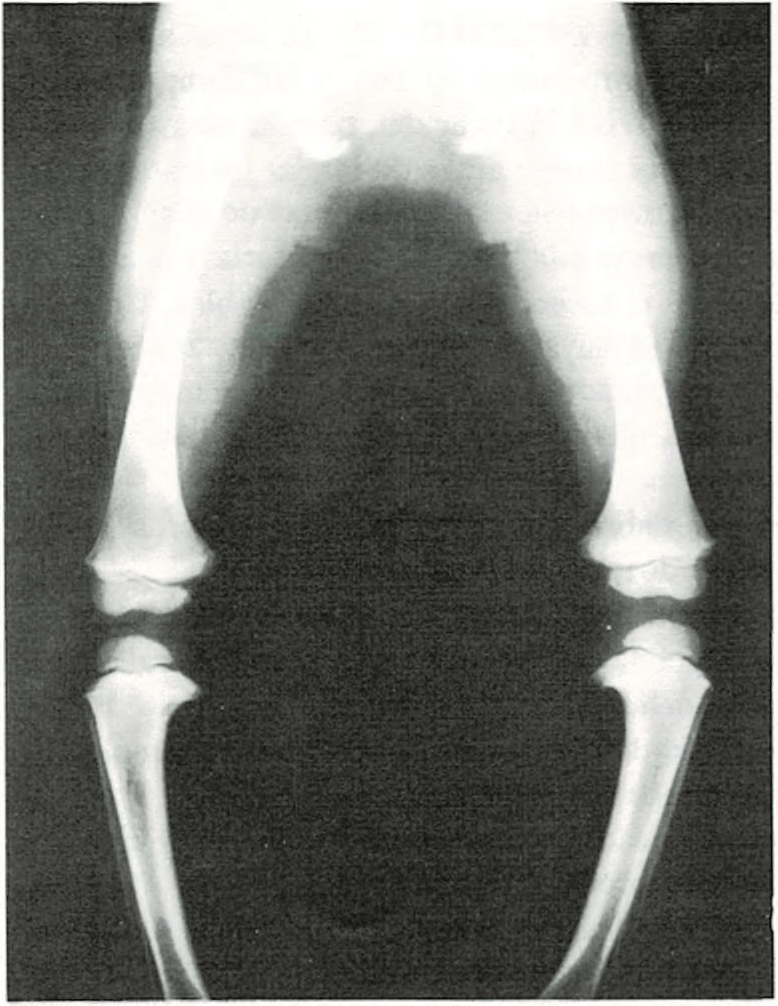

Piernas arqueadas.

Casi todos los recién nacidos parecen tener las piernas curvas. Las rodillas

se hallan dirigidas hacia fuera y los pies ligeramente vueltos hacia dentro. A pesar de que los huesos generalmente están bien formados, las piernas tienden a seguir adoptando la posición que tenían en el claustro materno.

Las piernas curvas no desaparecen en el niño hasta al cabo de un cierto tiempo de caminar. Deben enderezarse primero el tobillo y los músculos del pie, así como los músculos y ligamentos de sus piernas y rodillas. A medida que los músculos se fortalecen al andar, las piernas van apareciendo más rectas y las rodillas más juntas. La edad media en la cual desaparece la incurvación de las piernas es entre 1 y 2 años.

Si tiene las piernas excesivamente incurvadas o si a los dos años no se han enderezado, se consultará al médico.

En algunos casos, las piernas incurvadas pueden estar provocadas por un raquitismo, producido por deficiencia alimenticia de vitamina D. Sólo raramente será necesario un tratamiento especial con ortopedia o cirugía.